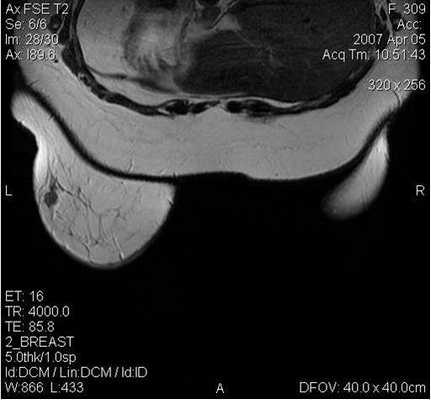

Поскольку традиционный маммографический скрининг у женщин до 40 лет малоэффективен, для скрининга может понадобиться альтернативная методика — МРТ. Современная контрастная магнитно-резонансная томография — высокочувствительный метод диагностики заболеваний молочной железы.

У женщин с мутациями BRCA1 или BRCA2 при проведении МРТ возможно диагностировать рак молочной железы на самых ранних стадиях.